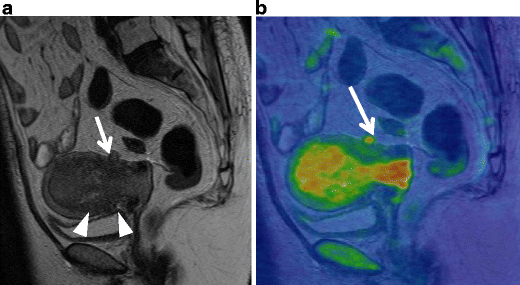

Endometrial stromal sarcoma in a 47-year-old woman. a Sagittal T2-weighted image demonstrates an ill-defined lesion of slightly increased intensity in the posterior myometrium of the uterus (arrows). Note the bands of low signal intensity within the lesion, which represent preserved myometrial bundles amidst the infiltrating nests of tumors cells. b Fusion image with DWI onto T2-weighted image reveals increased signal corresponding to the infiltration tumor in the myometrium